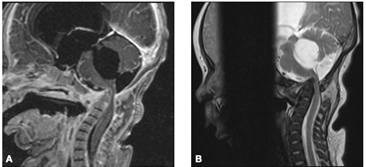

En el control a los 6 meses de vida, presenta buen crecimiento y desarrollo, aunque con alguna dificultad para lograr el sostén cefálico. Del examen físico del aparato osteoarticular se destacan movimientos de flexo-extensión y rotaciones de cuello tanto activos como pasivos; mantiene la dismetría de los miembros inferiores de aproximadamente 2 cm, sin dolor a la movilización de los mismos. De la imagenología, la RNM cervical presenta recesión del proceso inflamatorio prevertebral, así como un descenso de C1-C2 sobre el tronco encefálico; mientras que en la radiografía de pelvis mantiene la luxación de la cadera izquierda con una disminución de la reacción perióstica metafisaria (Figura 5).

Figura 5: A: Corte sagital en secuencia STIR de RNM, se observa recesión del proceso inflamatorio prevertebral, asi como un descenso de C1-C2 sobre el tronco encefálico. B: Radiografía AP Pelvis, mantiene la luxación de la cadera izquierda con una disminución de la reacción perióstica metafisiaria.